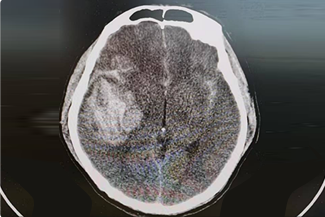

神經(jīng)創(chuàng)傷與重癥中心主要是針對神經(jīng)系統(tǒng)疾病的急危重癥患者進行全面地救治,涉及顱腦創(chuàng)傷以及出血的各種常規(guī)開顱、顯微/內(nèi)鏡下顱底修復與重建、復合手術(shù)、復雜的腦積水和顱面骨缺損修復成形手術(shù)、綜合治療神經(jīng)系統(tǒng)感染等。

擅長腦血管病(出血與缺血)的神經(jīng)介入與微創(chuàng)手術(shù),能熟練開展腦外傷、重度顱腦損傷的救治工作。